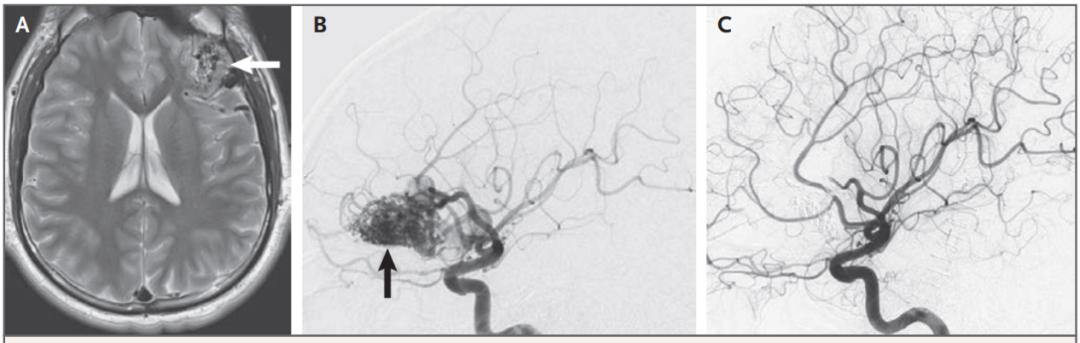

(4)影像学检查:CR和MRI平扫可以提供一些信息,如CT上可能出现代表畸形血管团的密度增高区等,诊断的金标准为DSA。

图6 体检发现22岁无症状动静脉畸形患者[A]MRI提示左侧额叶[B]患者左侧大脑中动脉由静脉供血[C]术后造影显示无畸形血管团残留(5)治疗:手术治疗是唯一完全消除畸形血管团和动静脉分流的方案,可根据具体情况选择手术切除、立体定向放射治疗(SRS)或血管内栓塞等。未破裂动静脉畸形患者也可选择保守治疗。